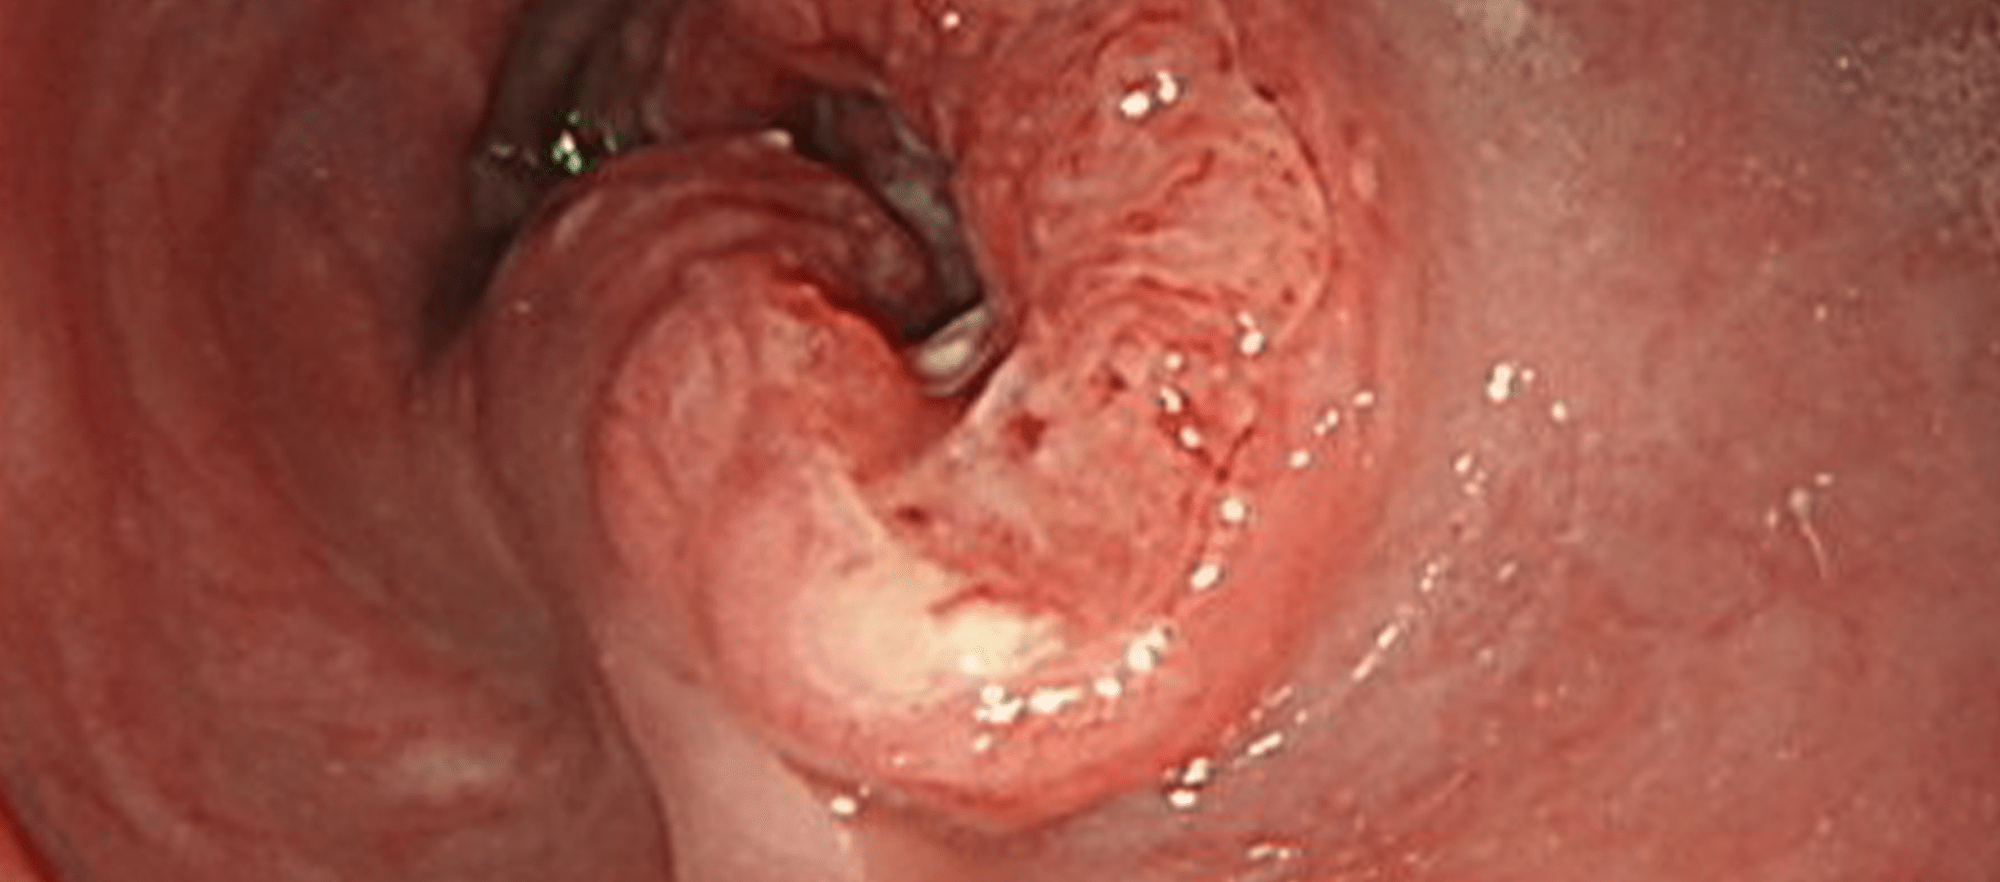

胃アニサキス症

間欠的なみぞおちの激痛や吐気、蕁麻疹などが引き起こされます。アニサキスが寄生している魚介類を、加熱処理が不十分なまま摂取したことが原因となります。